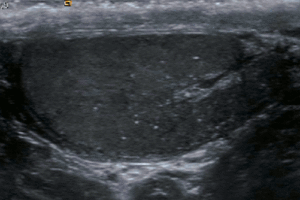

Testicular microlithiasis is an unusual condition diagnosed on testicular ultrasound. It is found in between 1.5 to 5% of normal males, and may be found in up to 20% of individuals with subfertility. It is an asymptomatic, non-progressive disease. The cause is unknown, but this condition has been associated with testicular cancer in a small group of individuals, cryptorchidism, mumps, infertility and intraepithelial germ cell neoplasia. Classic testicular microlithiasis is defined as five or more echogenic foci per view in either or both testes, and limited testicular microlithiasis defined as one or more echogenic foci that do not satisfy the criteria for classic testicular microlithiasis. In 80% of cases, both testicles are affected.